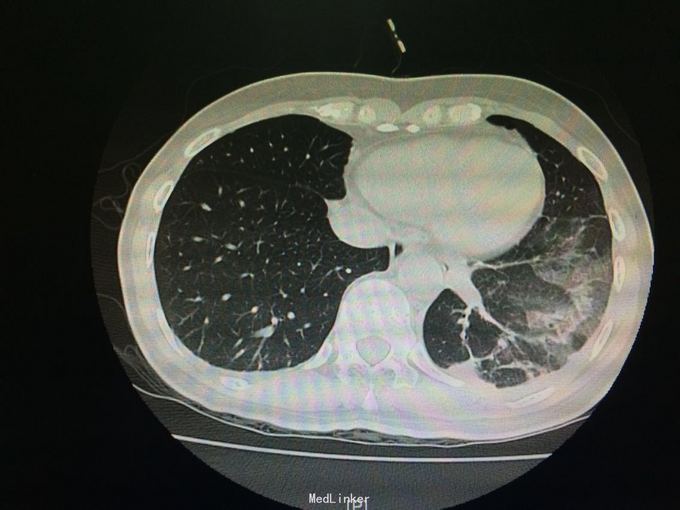

随访:夹管24h后查胸部CT示:左肺下叶炎症、左侧胸腔少量积气、积液。 讨论:该患者是否需要继续闭式引流排气,是否需继续抗生素治疗?